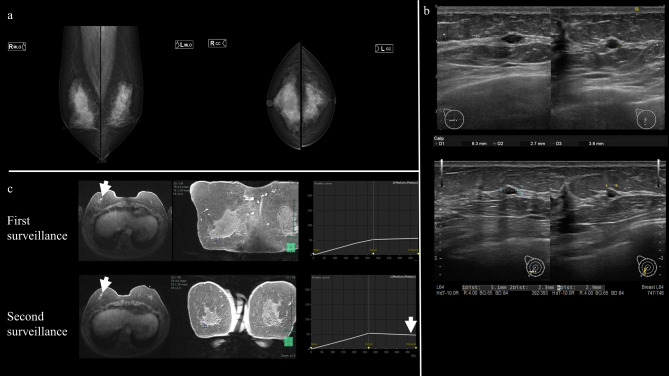

Case presentation: The patient was a 63-year-old woman. Her sister had a history of breast cancer in her 30s and was found to be a BRCA2 pathogenic variant carrier by genetic testing. The patient therefore presented to the genetic department of our hospital and underwent genetic testing (out-of-pocket). A pathogenic variant was found at the same site. During annual breast and ovarian surveillance at the patient's own expense, a physician with sufficient expertise in contrast-enhanced breast magnetic resonance imaging (MRI) noticed a change in the contrast enhancement pattern on breast MRI and performed needle biopsy, revealing ductal carcinoma in situ. At the request of the patient, she underwent concurrent contralateral risk-reducing mastectomy and risk-reducing salpingo-oophorectomy in addition to breast cancer treatment.